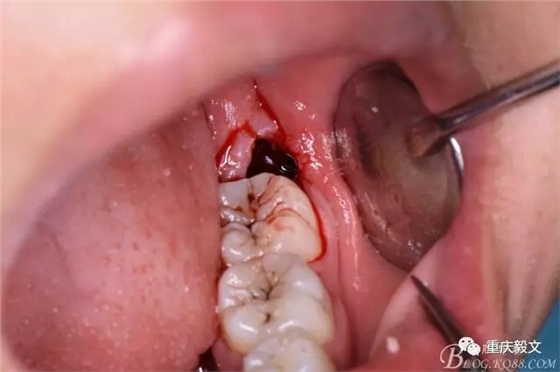

圖8.先從頸部橫斷38

圖9.再把38牙冠近遠中縱斷

圖10.用丁字挺取出牙冠舌側(cè)部分

圖11.取出的38舌側(cè)部分

圖12.接著取出38的頰側(cè)部分牙冠